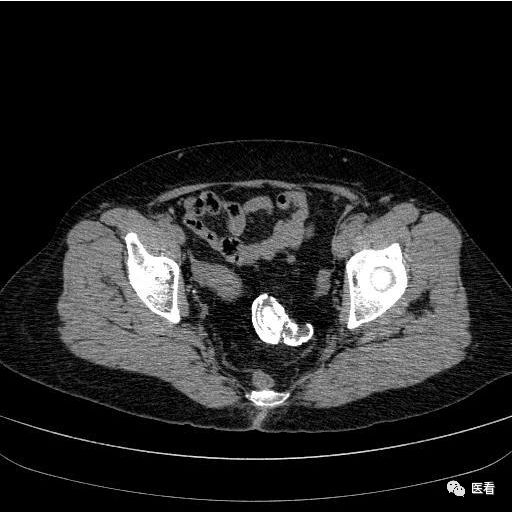

再来看看下面这例67岁女性患者,体检发现盆腔病变,图片比较多,或许可以帮大家更全面地了解▼(再次注意这不是子宫肌瘤钙化!)该病例来源于医看。

发现腹部巨大高密度的骨化、钙化结构,局部形态类似骨骼。可能有的医生可能会往这方面想,这不会是一个“胎儿”吧!

对!这就是石胎(lithopedion,stone babies)!

这是一种非常罕见的妊娠,Albucasis 首先报道了石胎,至今文献报道仅有 300 余例!这类患者多见于经济条件差和长期不做体检的女性。当孕妇胎儿在腹腔内死亡后,母亲的妊娠现象就会自动消失,月经恢复来潮,可无任何不适症状。胎儿在体内逐渐钙化,形成石胎。当然甚至有一部分患者都不知道自己怀孕,十几年后或死后才会被发现。